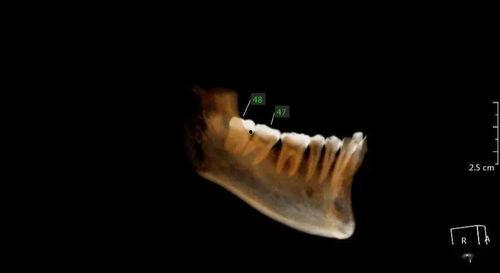

2021年的数据显示,智齿的分布情况因人而异。有些人长出了四颗智齿,而有些人可能一颗都没有。智齿的形态也各不相同,有的长得规规矩矩,有的却歪歪扭扭,甚至有的智齿长成了“倒钩”。

说到智齿,不得不提的就是疼痛。2021年,许多网友在社交媒体上分享了自己拔智齿的经历,其中不乏痛苦不堪的描述。智齿疼痛的原因有很多,比如智齿阻生、智齿发炎、智齿与邻牙拥挤等。

2. 拔除智齿:如果智齿引起疼痛或炎症,应及时拔除。